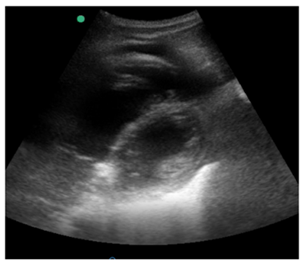

Caso clínico para responder à questão.

Uma paciente de 75 anos de idade, com diabetes, hipertensão

e histórico prévio de artroplastia total de joelho direito, foi

admitida no hospital após queda de própria altura e fratura de

fêmur distal direito. A cirurgia ortopédica foi realizada sem

intercorrências. No quinto dia de pós-operatório, observou-se

no monitor FC = 120 bpm, PA = 80 mmHg x 52 mmHg,

tempo de enchimento capilar maior que 4 segundo,

rebaixamento de consciência, turgência jugular importante,

ausculta respiratória com murmúrio vesicular bilateral e sem

ruídos adventícios. Então, decidiu-se realizar um

ecocardiograma beira-leito, cujo resultado é a imagem

mostrada a seguir na janela para esternal eixo curto.